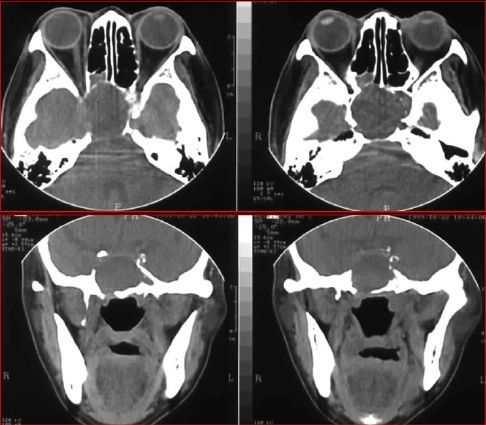

急性鼻窦炎

筛窦异物伴急性感染